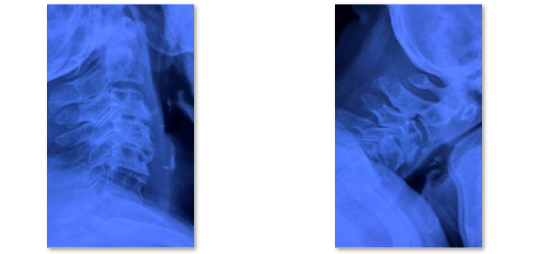

颈椎管狭窄症也是中老年人常见脊柱疾病,在椎管狭窄症发病率中仅次于腰椎管狭窄症。颈椎管狭窄症:构成颈椎管各解剖结构因发育性或退变因素造成骨性或纤维性退变引起一个或多个节段官腔狭窄导致脊髓血液循环障、脊髓及神经根压迫症者为颈椎管狭窄症。主要症状为1.感觉障碍:四肢麻木、过敏或疼痛,胸腹骨盆区发紧(束带感),严重者可有呼吸困难;2.运动障碍:四肢无力、僵硬不灵活,多数有下肢无力沉重、脚落地似踩棉花感,站立不稳,加重可出现四肢瘫痪;3.大小便障碍。颈椎管狭窄症患者CT或MRI通常表现为多节段颈椎间盘突出、黄韧带增生肥厚,颈椎椎管容积大大减小,脊髓多节段受压。

术前